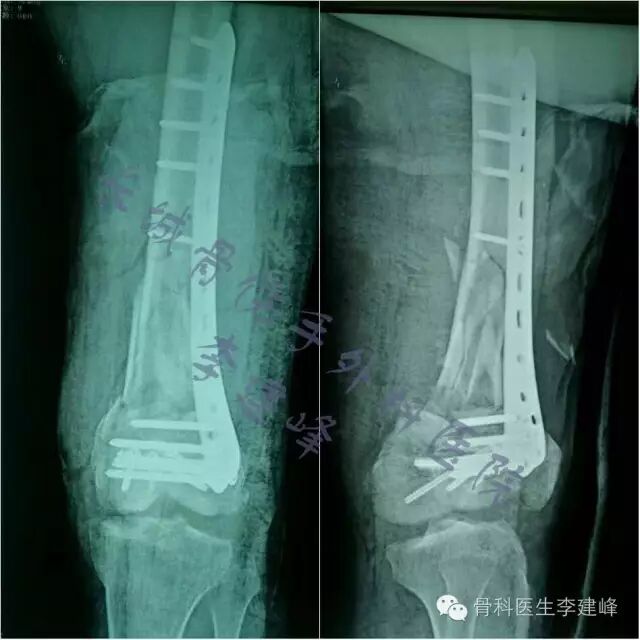

Four case:

术前

术后